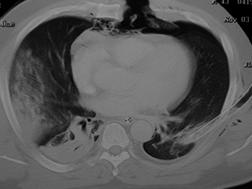

TRAUMATISME TORACICE

Aspect radiologic Imagine CT

Pneumotorace sufocant bilateral Pneumotorace sufocant stang

Imagine

CT Imagine CT

Contuzie pulmonara stanga Contuzie pulmonara dreapta

Contuzie pulmonara dreapta.Imagine CT